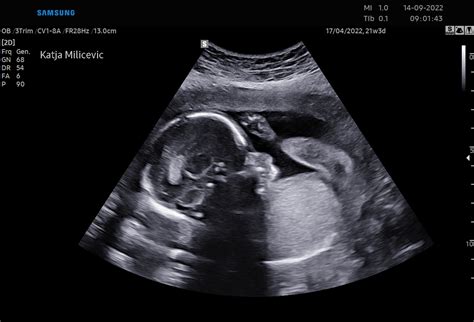

Nuhalna svetlina predstavlja pomemben ultrazvočni presejalni pregled v zgodnji nosečnosti, s katerim strokovnjaki skrbno ocenjujejo tveganje za morebitne kromosomske nepravilnosti ploda. Ta ključni postopek se običajno opravi med 11. in 14. tednom nosečnosti, ko so parametri ploda že dovolj razviti za natančno merititev. Zanimivo je, da ta pregled krije ZZZS iz obveznega zdravstvenega zavarovanja, kar pomeni, da za napotitev nanj ne potrebujete posebne napotnice, temveč se lahko neposredno obrnete na izvajalca.

Nuhalna svetlina je v svojem bistvu ultrazvočni presejalni test, ki omogoča zgodnje odkrivanje potencialnih tveganj za kromosomske nepravilnosti ploda. Med samim pregledom z ultrazvokom zdravnik natančno izmeri debelino tekočine, ki se nahaja na zatilju ploda - to je tisto, čemur pravimo nuhalna svetlina. Povečana vrednost te meritve lahko namreč nakazuje na večje tveganje za določene kromosomske nepravilnosti, kot so:

Poleg natančne meritve nuhalne svetline, zdravnik opravi poglobljen ultrazvočni pregled, med katerim izmeri še več ključnih parametrov ploda. Ti vključujejo:

- Razdaljo teme-trtica (CRL): Ta meritev omogoča določitev gestacijske starosti ploda in je en izmed osnovnih parametrov za oceno rasti.

- Srčni utrip ploda: V tem zgodnjem obdobju je srčni utrip pomemben pokazatelj vitalnosti ploda.

- Premer plodove glavice: Pomaga pri oceni rasti in razvoja ploda.

Na podlagi teh natančnih meritev, skupaj s starostjo nosečnice, računalniški program izračuna individualno tveganje za morebitne kromosomske nepravilnosti ploda. Ta statistični pristop omogoča bolj personalizirano oceno tveganja.